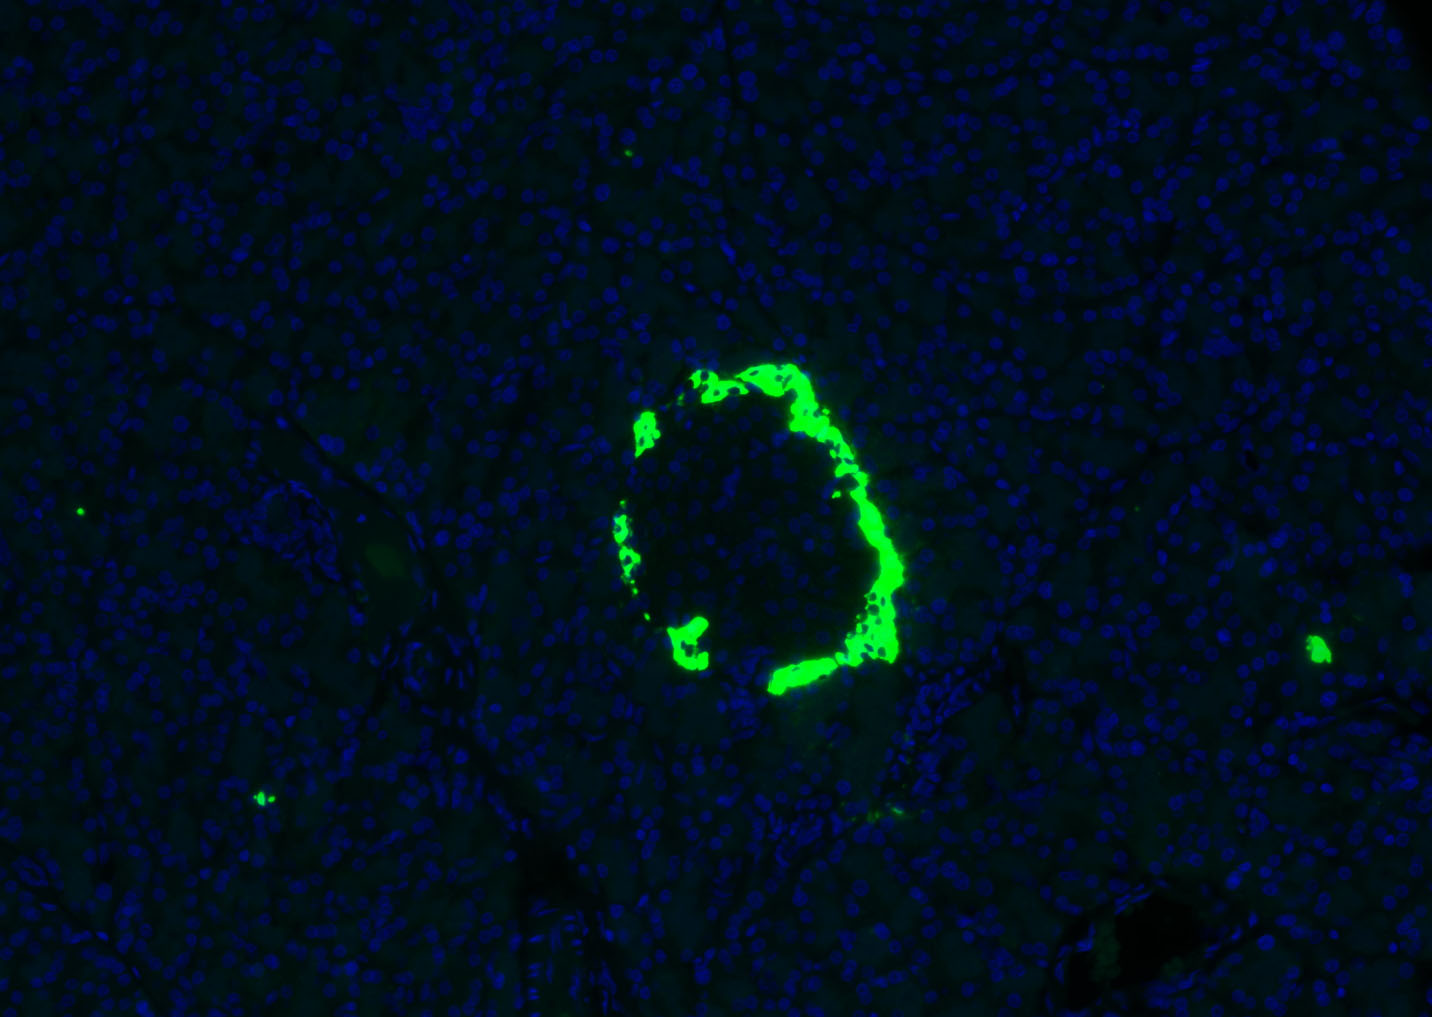

產(chǎn)品圖片

Paraformaldehyde-fixed, paraffin embedded (mouse pancreas); Antigen retrieval by boiling in sodium citrate buffer (pH6.0) for 15min; Blocking buffer (normal goat serum) at 37°C for 30min; Antibody incubation with (Glucagon) Polyclonal Antibody, Unconjugated (bs-3796R) at 1:500 overnight at 4°C, followed by a conjugated Goat Anti-Rabbit IgG antibody (YF488) for 90 minutes, and DAPI for nuclei staining.

Paraformaldehyde-fixed, paraffin embedded (rat pancreas); Antigen retrieval by boiling in sodium citrate buffer (pH6.0) for 15min; Blocking buffer (normal goat serum) at 37°C for 30min; Antibody incubation with (Glucagon) Polyclonal Antibody, Unconjugated (bs-3796R) at 1:300 overnight at 4°C, followed by a conjugated Goat Anti-Rabbit IgG antibody (YF488) for 90 minutes, and DAPI for nuclei staining.